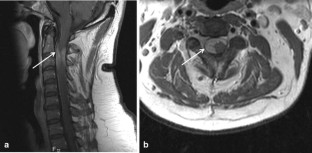

Fig. 1

Fig. 2